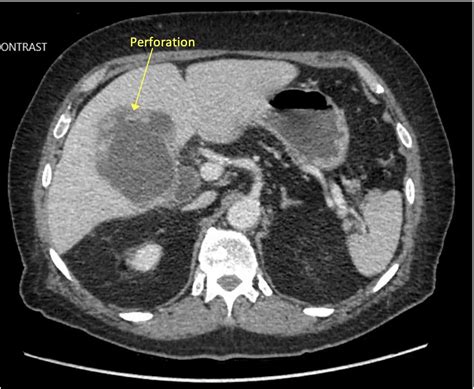

CT Scan Provides more detailed images; often used to identify free fluid or air in the abdominal cavity indicating perforation.